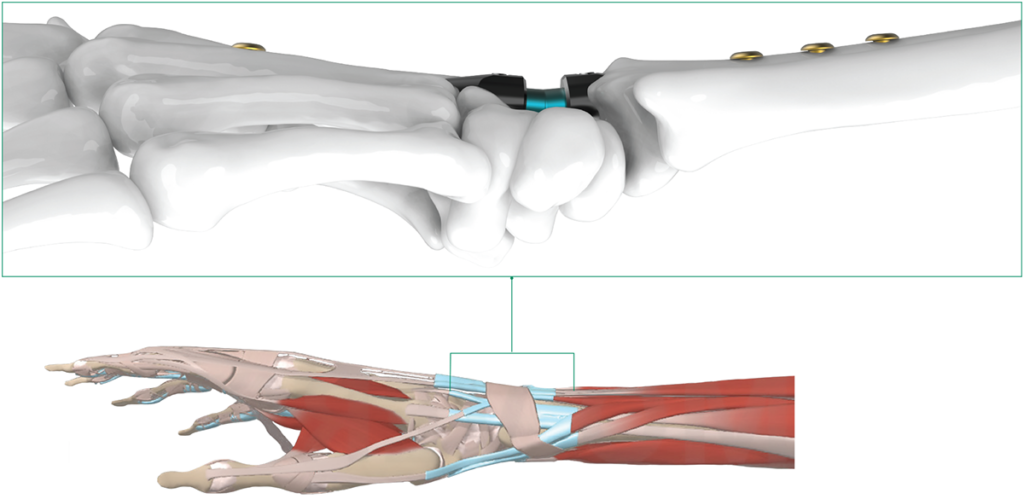

- Placement of the intramedullary device minimizes irritation to the soft tissue

Intramedullary placement minimizes soft tissue irritation

Alternate Wrist Fusion Plating Construct

Alternate Wrist Fusion Plating Construct

Wrist arthrodesis is a surgical procedure in which the wrist joint is fused together. A wrist arthrodesis plate is designed to stabilize the wrist joint after wrist fusion.The plate is fixed to the bones with nails, such as IMPLATE®, which provides compression and stability to the fused joint. Wrist plating systems are commonly used to treat:

The plate can be placed on the dorsal (back) or volar(front) side of the wrist, depending on the patient’s condition and the surgeon’s preference.